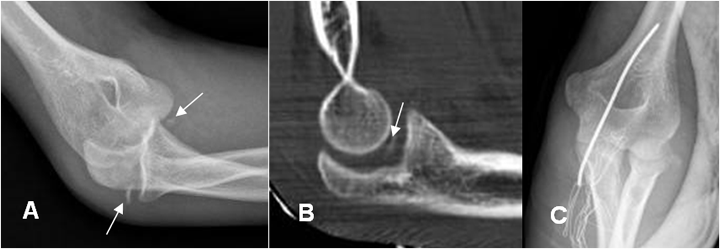

Fig 32. Cambios postQx.

A: Rx oblicua. Luxofractura del codo, con fragmentos libres en la parte medial y lateral.

B: TAC reconstrucción sagital. Luego de la reducción, se identifica cuerpo libre intra-articular.

C: Rx AP. Fijación posterior con aguja y alambre.